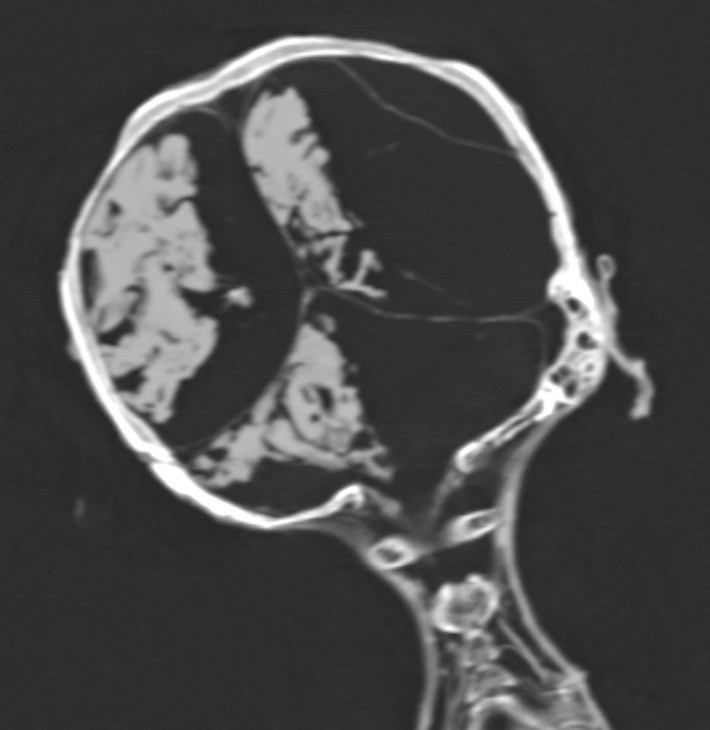

Xác ướp khiến giới chuyên gia ám ảnh bởi được bảo quản nguyên vẹn trong tư thế đầu ngửa ra sau và miệng há to như đang thét lên vì sợ hãi.

Theo đó, xác ướp được bảo quản theo đúng tư thế lúc qua đời: đầu ngửa ra sau và miệng há to như đang thét lên trong đau đớn.